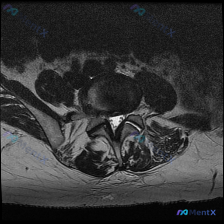

看到这张腰椎MRI T2轴位片,整理一下完整的分析思路分享给大家。 病例基础信息 这是一例腰椎MRI T2序列轴位影像,定位为下腰椎节段(L4/5或L5/S1,需结合矢状位确认),影像清晰显示椎体、椎间盘、椎管、硬膜囊、马尾神经、黄韧带、双侧关节突关节及椎旁肌肉结构。 核心影像发现 1. 椎间盘改变...

腰椎MRI轴位读片分享 今天拿到这个腰椎轴位T2加权MRI,正好整理一下读片和分析思路,分享给大家。 --- 病例影像基础信息 提供的是腰椎MRI T2加权轴位影像,没有侧位定位像和矢状位序列,我们先基于现有信息分析: 1. 定位:从椎体形态、关节突位置、硬膜囊结构来看,这个层面大概是L4/L5或者...